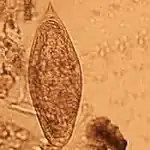

| Schistosoma intercalatum | 175 × 60 µm (140–240 × 50–85 µm). | Wydłużone, z tępym przednim końcem i zaostrzonym tylnym, zaopatrzonym w kolec. Niekiedy wrzecionowate. Żółte lub żółtobrązowe, w środku zawierają dojrzałe miracidium. | Kał | ![]() |